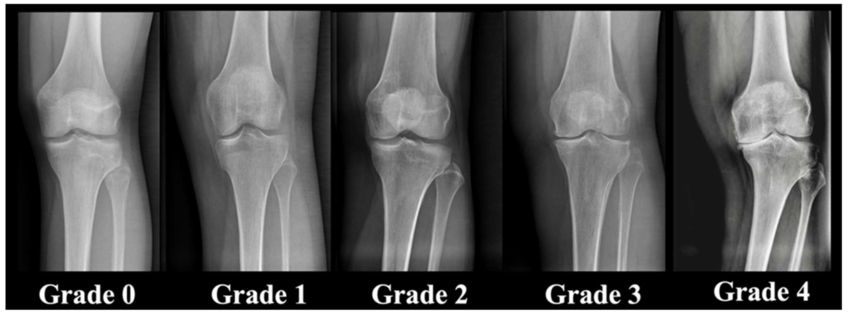

レントゲン画像で見る膝の進行度(ケルグレン・ローレンス分類)

ケルグレン・ローレンス分類は、イギリスの研究者ジョン・ケルグレンとジョセフ・ローレンスによって提案された国際的な基準で、レントゲン所見に基づいて膝の状態を評価します。膝の状態を数値的に把握できるため、医師や専門家との相談の際に共通の目安として役立ちます。

- Grade 0(正常):異常なし。

- Grade 1(疑い):ごく小さな骨棘(こつきょく:骨のトゲ状の変化)が見られる。症状は軽度。

- Grade 2(軽度):明らかな骨棘が確認され、関節隙がやや狭くなる。歩行や階段で痛みが出やすい。

- Grade 3(中等度):複数の骨棘と関節隙の明確な狭小化。強い痛みやO脚傾向が目立ち、生活に支障が出始める。この段階から膝に水がたまり始めることが多い。

- Grade 4(重度):関節隙がほとんど消失し、骨同士が接触。安静時にも痛みがあり、膝の関節を人工の関節に置き換える手術が検討される段階。

症状の進行段階とレントゲン画像で見る進行度をあわせて理解することで、自分の状態をより具体的にイメージしやすくなります。